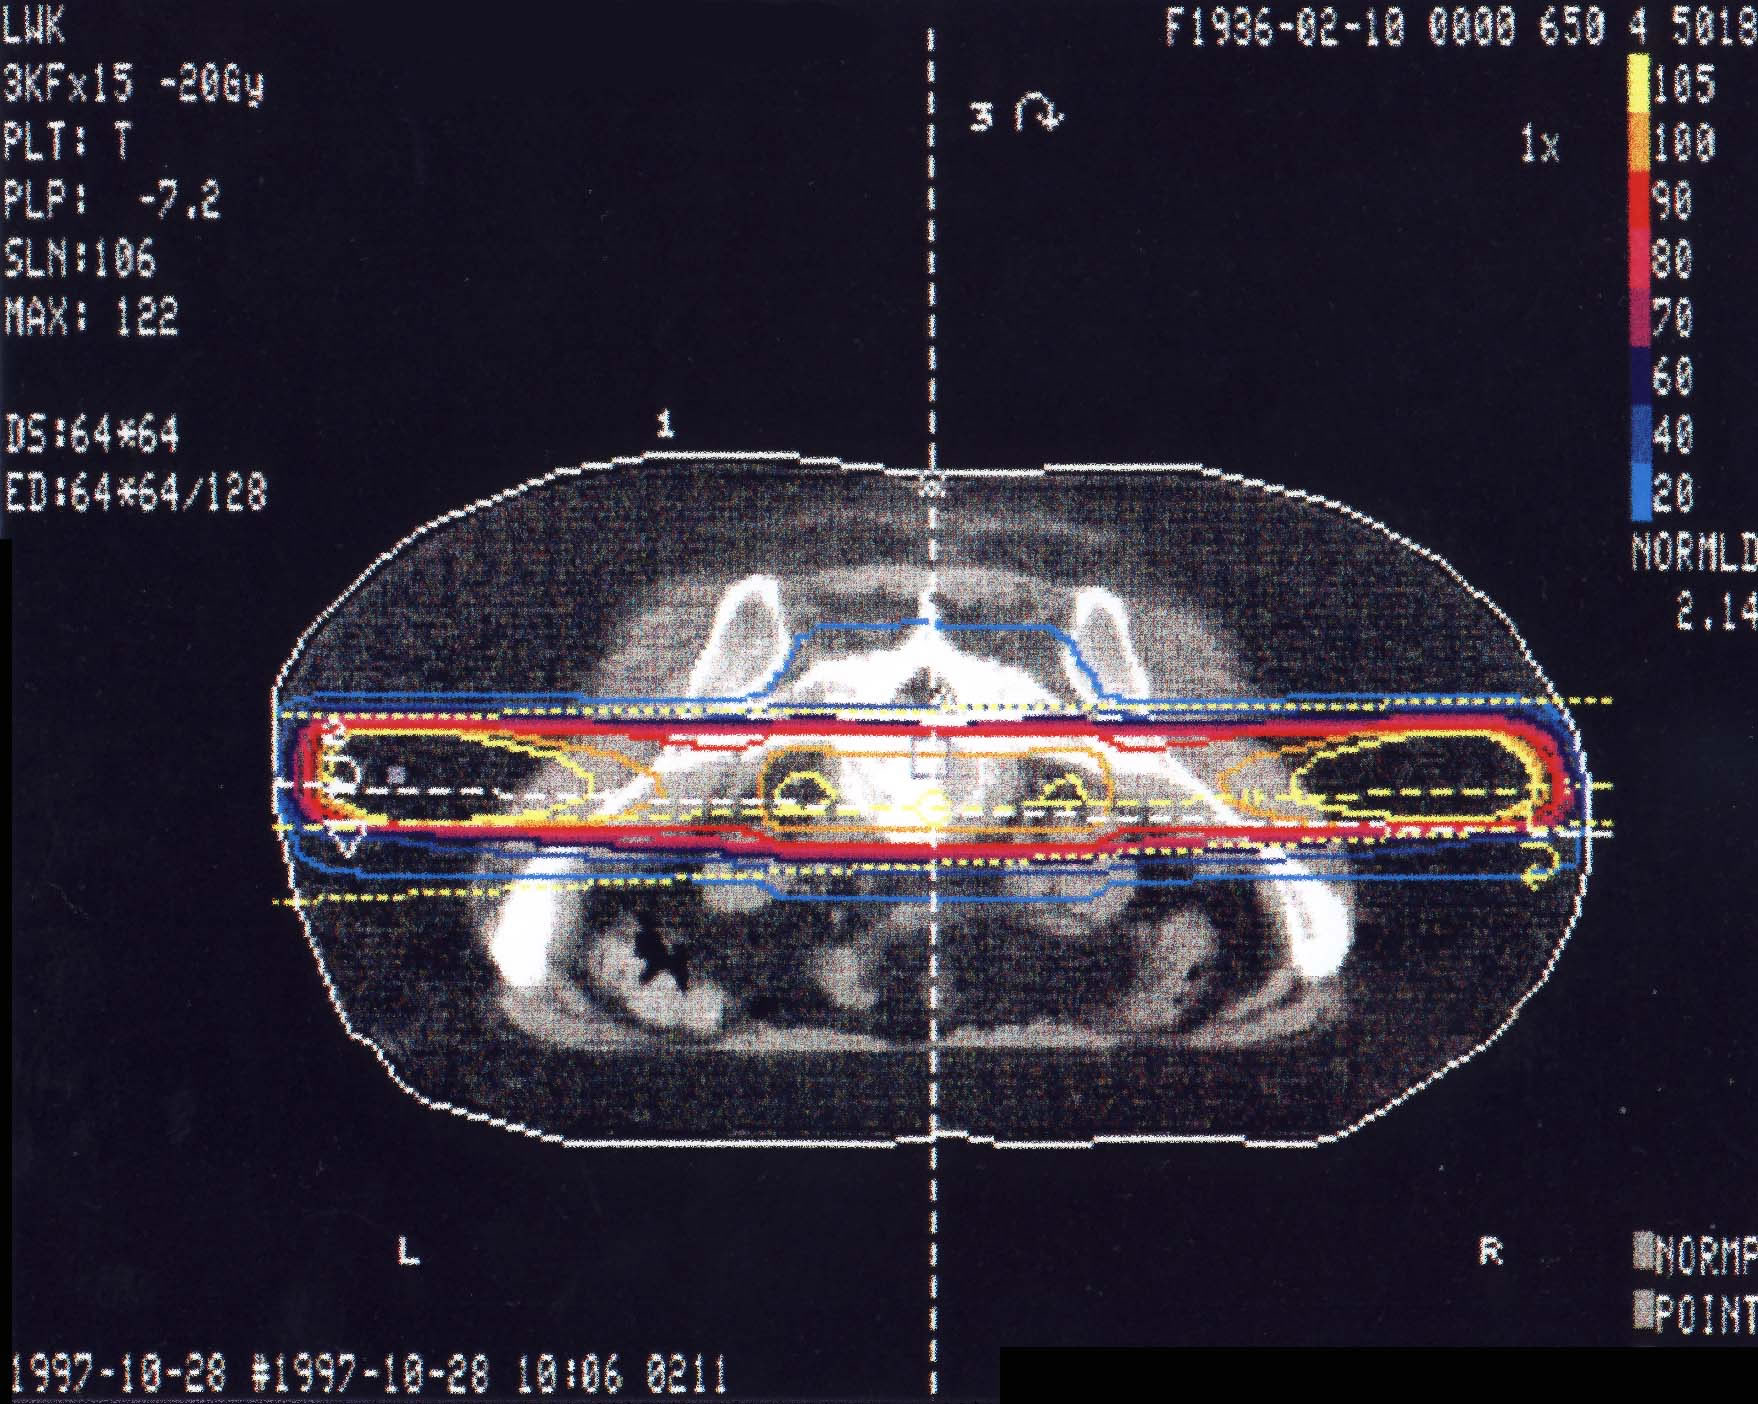

Tumore des Knochens: Bestrahlungsplan